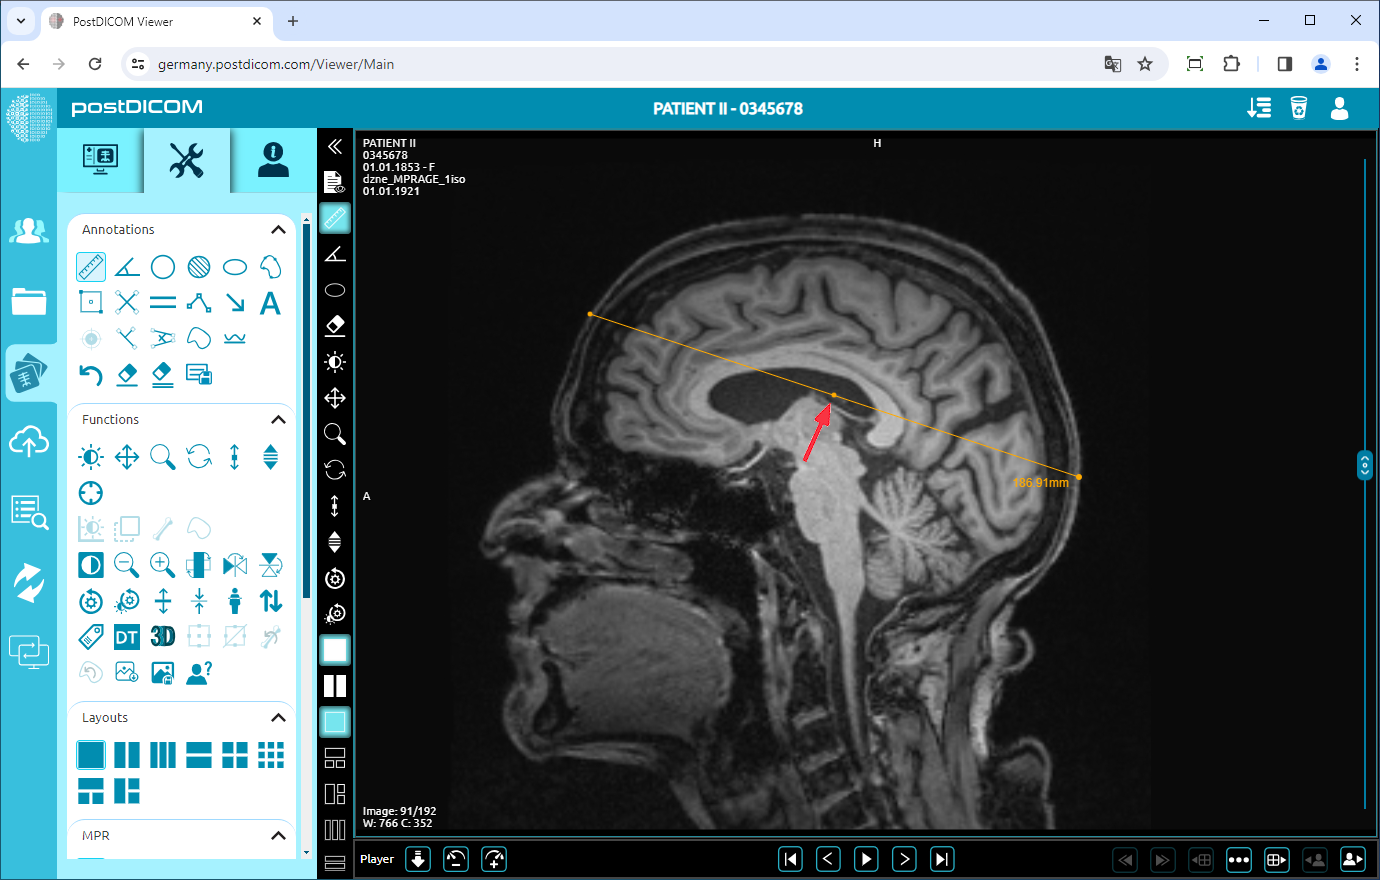

To move the line, right-click to exit from the function, click on the point in the middle of the line, and drag your mouse to the direction you want.

In this way, you can measure any distance on the view with its actual value.